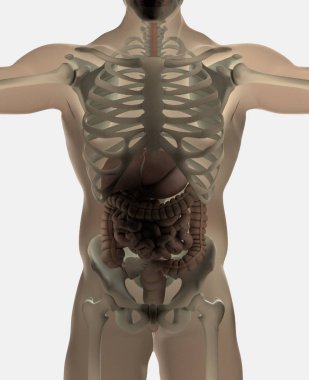

Sindirim Sistemi

En Çok Aranan Kelimeler

MaviresimlemeİnsanKadınSağlıkkanİlaçAğızSolunumerkekkalpgövdeMidebiyolojiBilimSistemözetorgİskeletanatomiKas gücübeyinSistemlersindirimGerginakciğerlerkaraciğerBöbrekiskeletOrganlaranatomikBağırsaklarBağırsakKolondolaşımdalakBenzer İçerikler